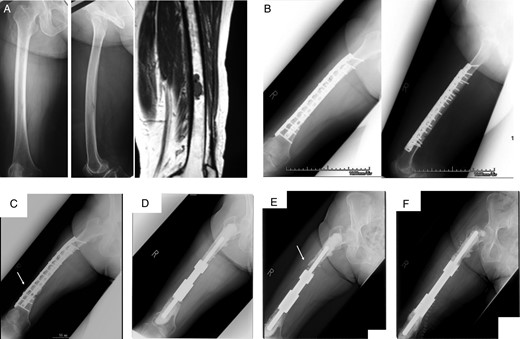

A 54-year-old male with primary soft tissue sarcoma. Plain radiograph (A) and CT (B) showing lytic destructive lesion in left femoral diaphyseal bone. T1- and T2-weighted magnetic resonance imaging (C) showing a soft tissue mass (20 × 20 × 12 cm) around femoral bone. Bone scintigraphy (D) showing increased uptake in femoral diaphyseal bone.

Case 2: A 71-year-old female was treated at the age of 68 for metastatic synovial sarcoma of the femur (Fig. 3A). Wide en bloc resection of the tumor and reconstruction with the use of IORBG were performed (Fig. 3B). At 32 months later, distal thigh pain due to fracture of the graft and breakage of plate occurred (Fig. 3C). Failed graft bone resection, implant removal and reconstruction with custom-made intercalary endoprosthesis were performed (Fig. 3D). The best MSTS score was 25 of 30. Aseptic loosening occurred at 29 months after the first endoprosthetic replacement which required a revision procedure (Fig. 3E and F). This was associated with osteolysis around the distal femoral end of the prosthesis.

A 68-year-old female with metastatic synovial sarcoma in right femoral diaphyseal bone. Plain radiograph and MRI (A) showing metastatic bone tumor. Radiograph (B) showing wide resection included femoral diaphyseal bone and reconstruction with IORBG and plate. At 32 months after surgery, radiograph (C) showing graft bone fracture (arrow) and reconstruction with intercalary endoprosthesis (D). Aseptic loosening occurred 29 months after surgery (E), and revision surgery was performed (F).